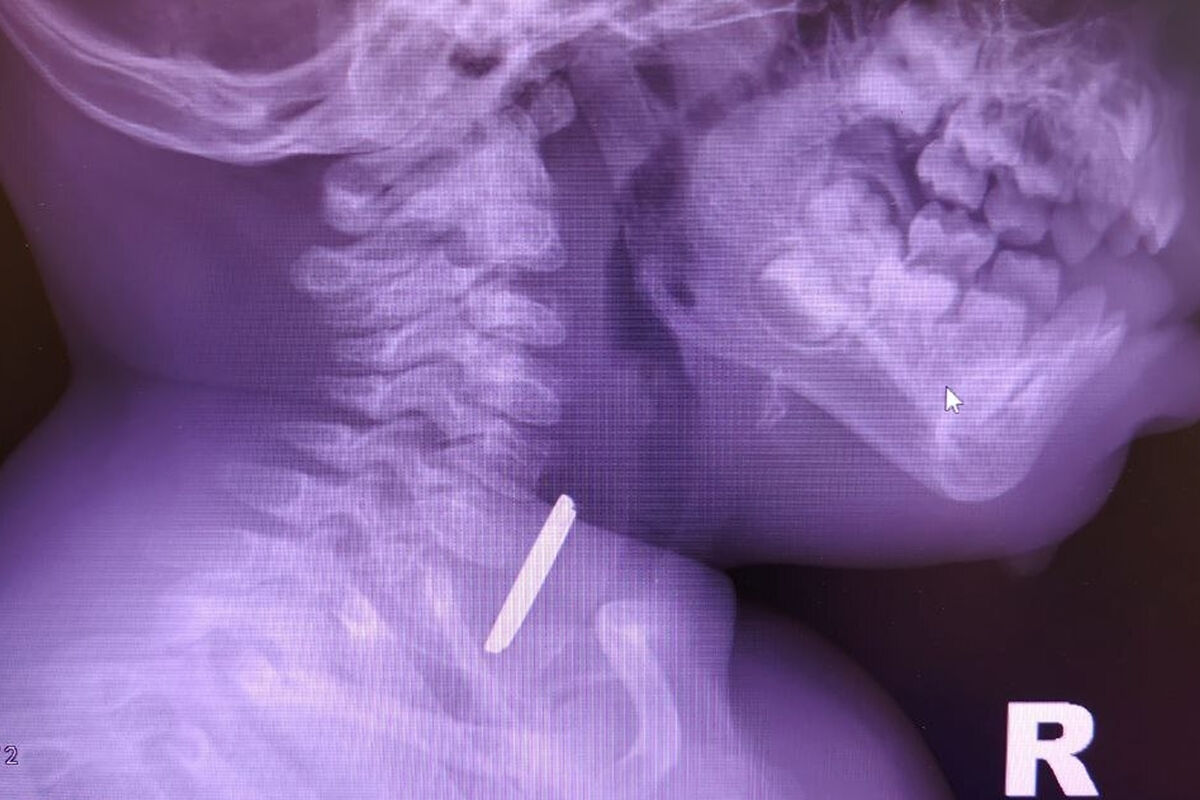

Маленький пациент поступил в больницу с затрудненным глотанием и слюноотделением. Ребенка направили на рентген, который показал наличие батарейки в верхней трети пищевода. Пациента направили направили на экстренную операцию, и под наркозом извлекли предмет, который уже успел причинить здоровью младенца вред.

«Батарейка повредила стенку пищевода, вызвав глубокий электрохимический ожог, занимающий половину просвета пищевода. Учитывая тяжесть состояния от полученной травмы, ребенок был госпитализирован в отделение реанимации, где проводилась интенсивная терапия», — рассказал детский хирург детской больницы Вячеслав Воронин.